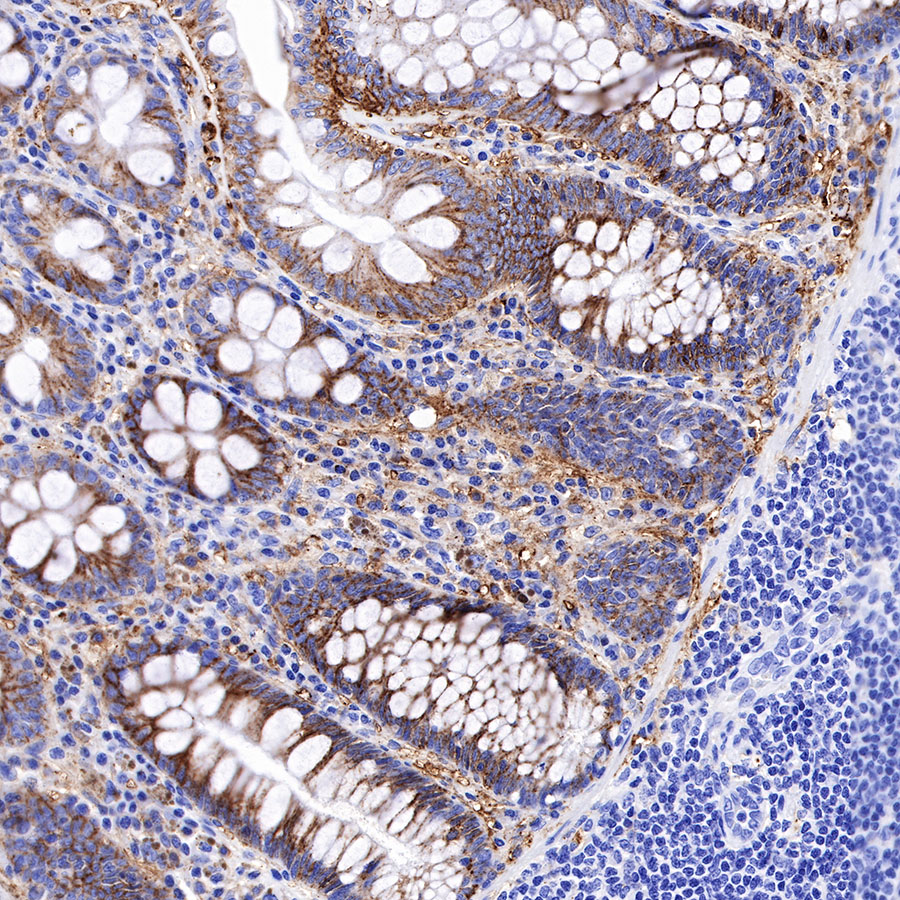

Syndecan-1 (CD138) is mostly restricted to epithelia, and bears heparan sulfate chains that are capable of interacting with a large array of polypeptides, including extracellular matrix components and potent mediators of proliferation, adhesion and migration. For this reason, it has been studied extensively with respect to carcinomas and tumor progression. Frequently, but not always, syndecan-1 levels decrease as tumor grade, stage and invasiveness and dedifferentiation increase. However, in some tumors, levels of syndecan-1 increase, but the characterization of its distribution is relevant. There can be loss of membrane staining, but acquisition of cytoplasmic and/or nuclear staining that is abnormal. Moreover, the appearance of syndecan-1 in the tumor stroma, either associated with its cellular component or the collagenous matrix, is nearly always a sign of poor prognosis [PMID: 33921767].

Immunohistochemistry